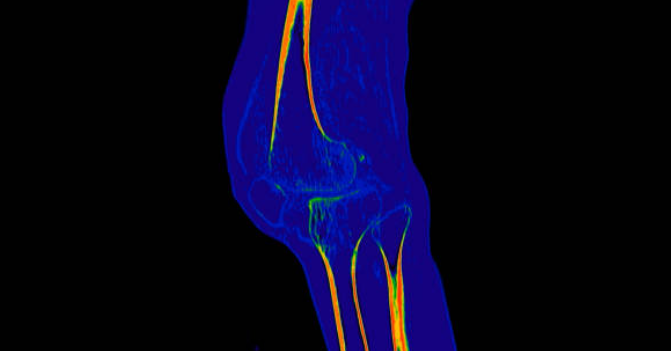

3. 골관절염

골관절염은 관절의 연골이 마모되어 관절 간의 마찰이 증가하는 질환입니다. 골관절염이 발생하면 무릎 안쪽 통증이 발생하며, 부기, 딱딱한 소리, 관절의 움직임 제한 등의 증상이 동반될 수 있습니다. 골관절염은 나이가 들면서 자연적으로 발생할 수 있으며, 비만, 과도한 운동, 외상 등의 요인이 영향을 줄 수 있습니다.